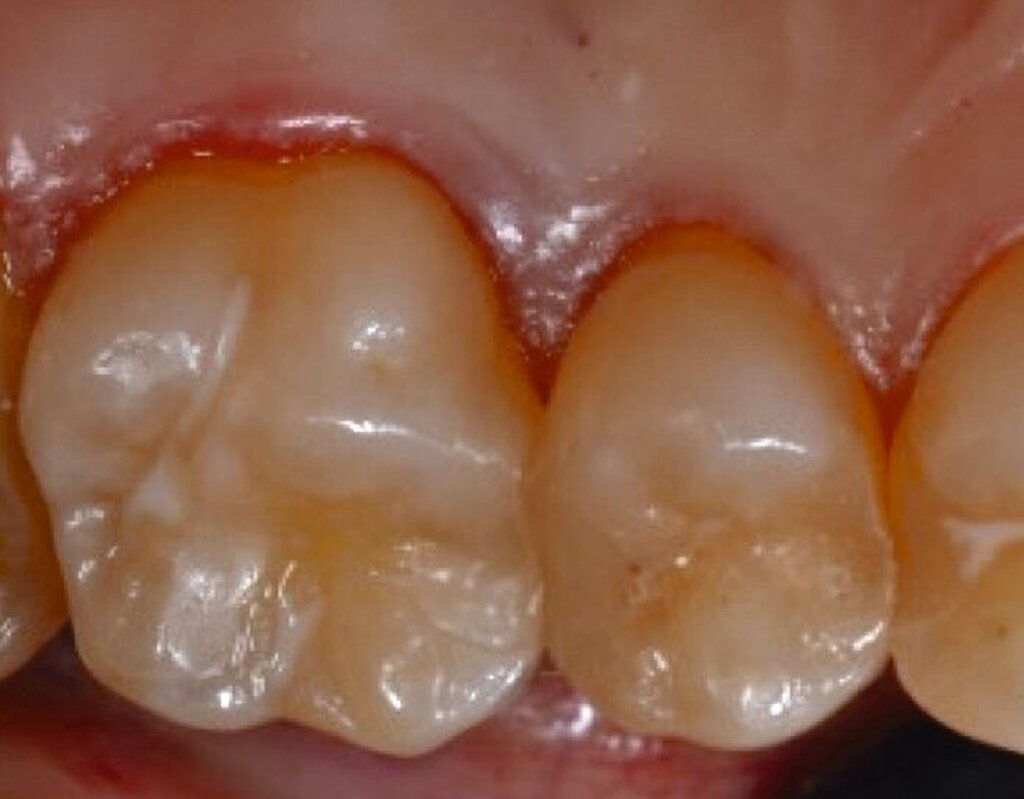

Fall 1 – einfach